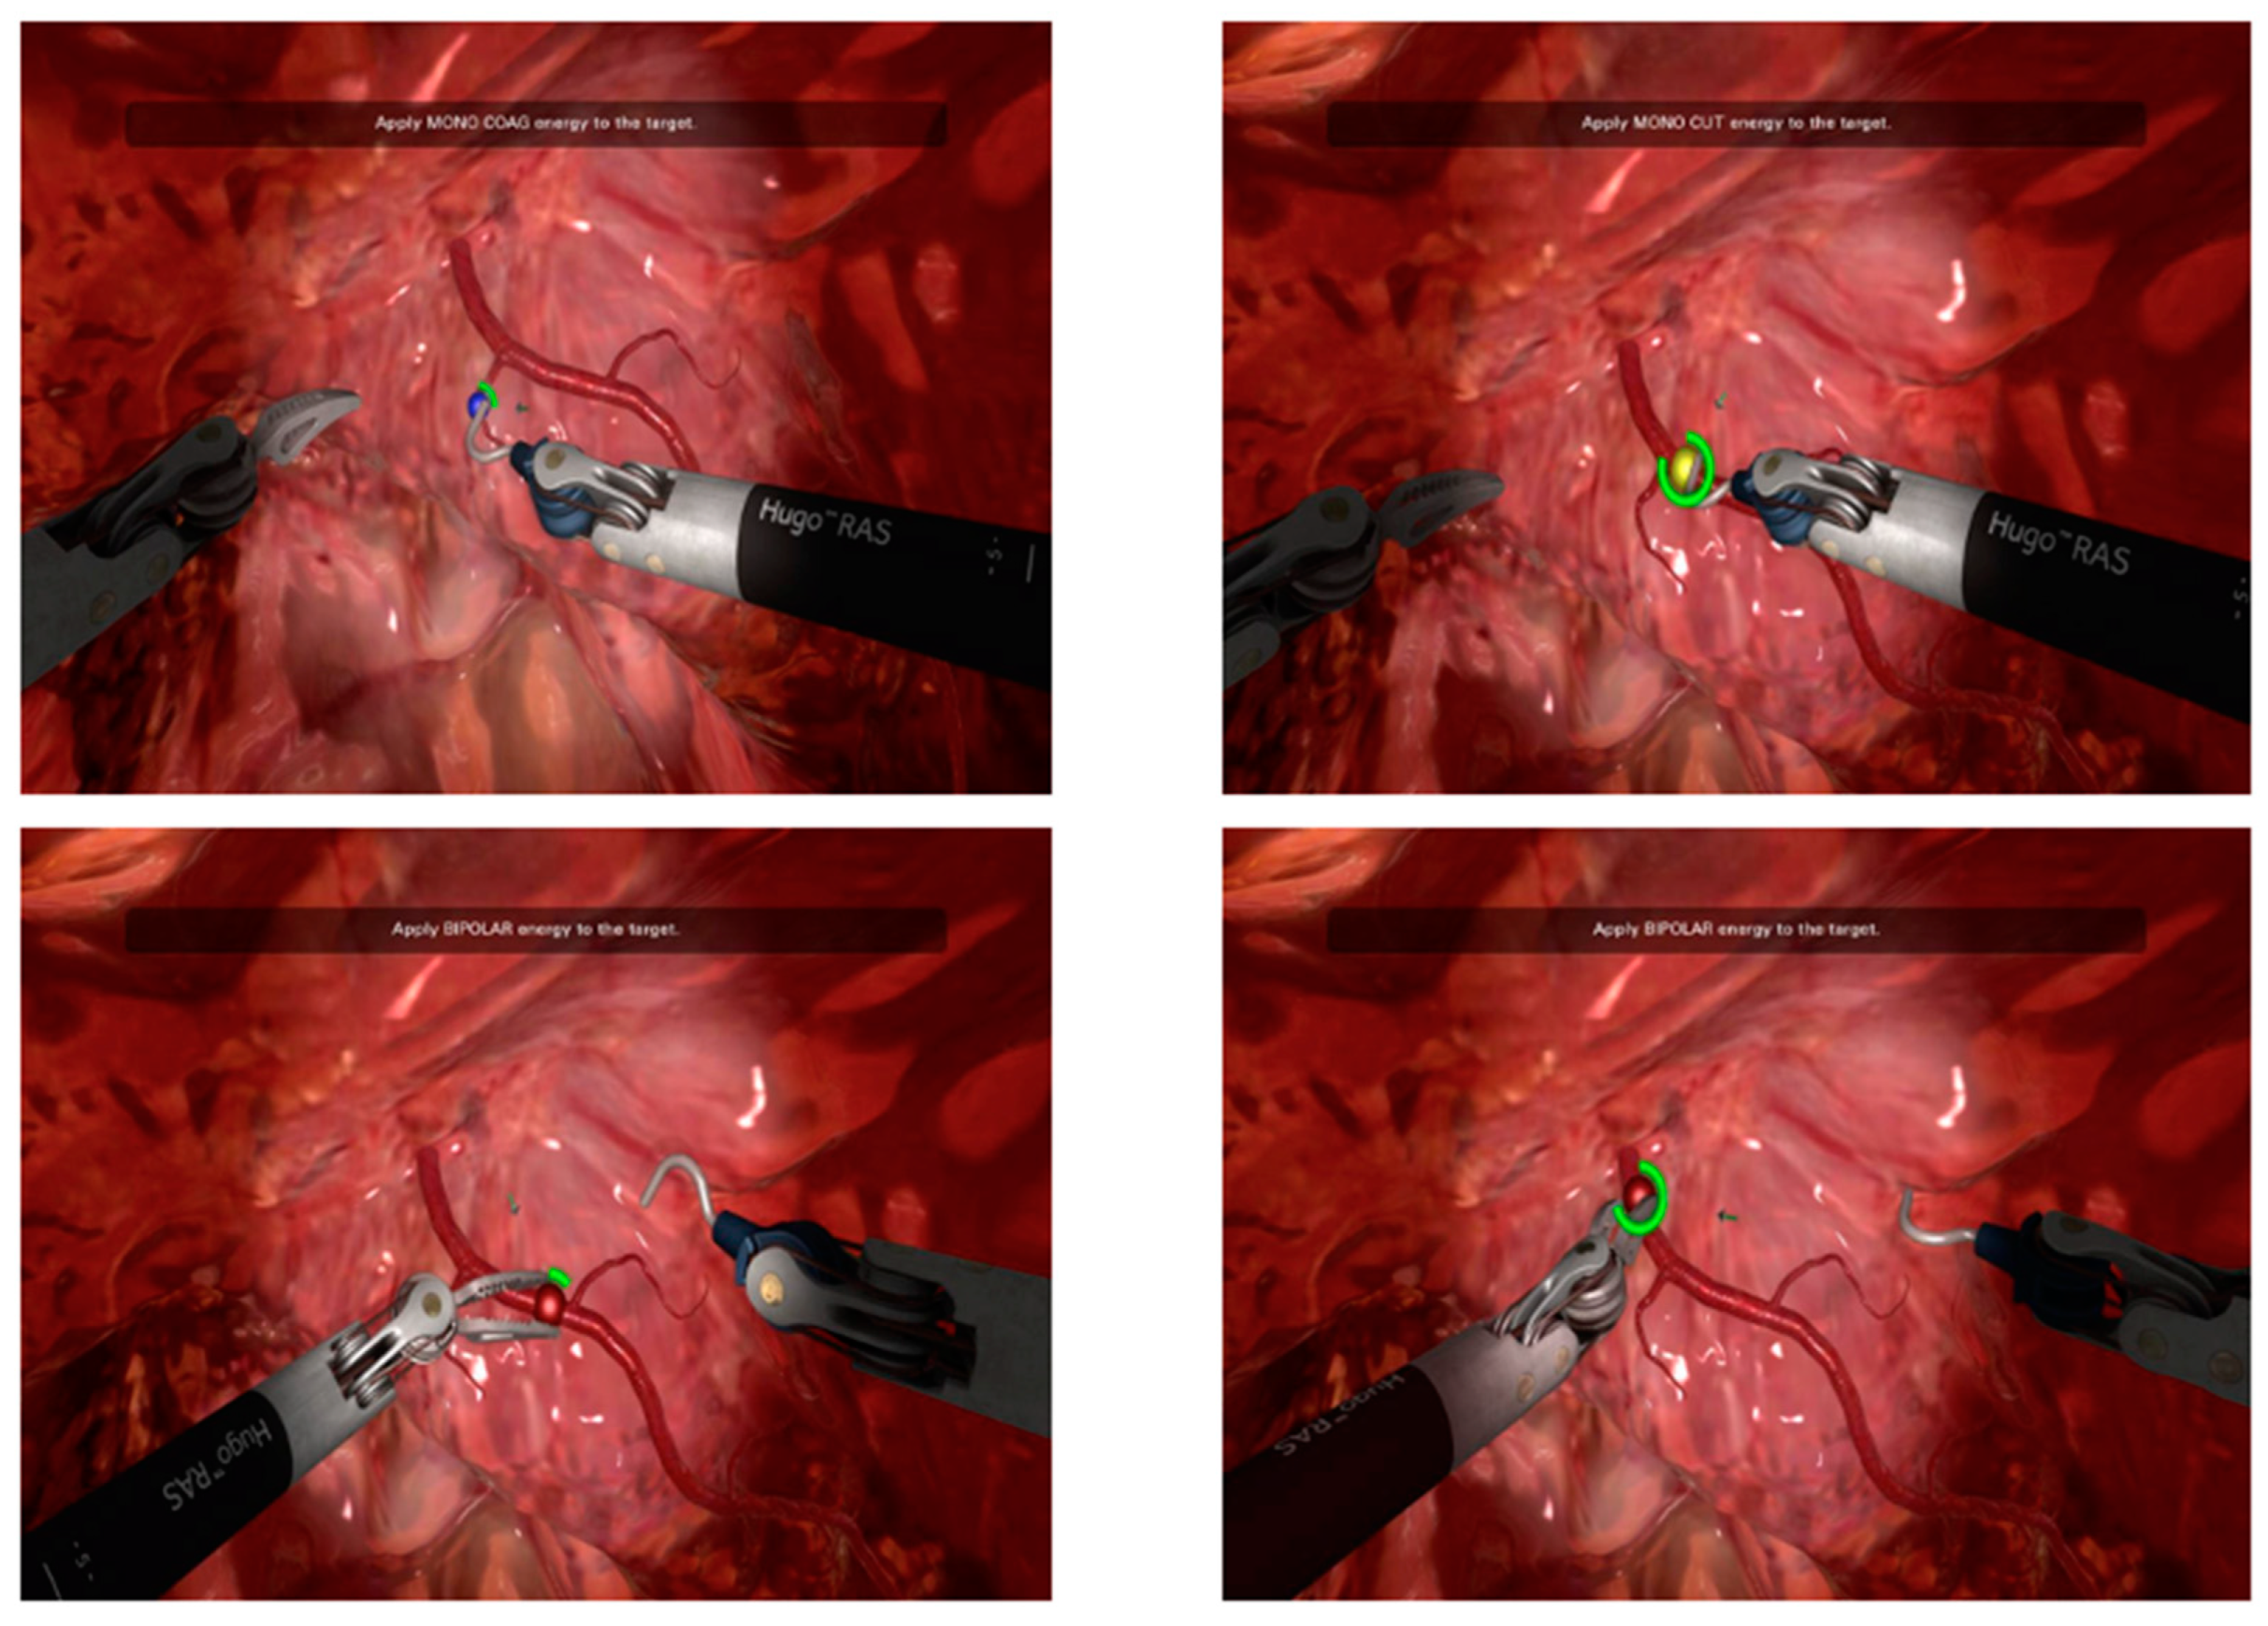

2.2. Training Session